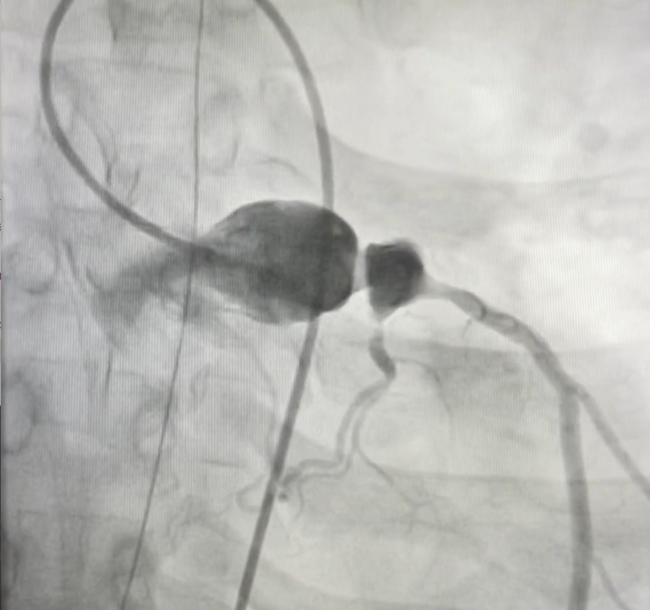

An 18-year-old man with past medical history of secondary arterial hypertension diagnosed at age 15 presented with an abdominal magnetic resonance imaging (MRI) that exhibited left renal artery stenosis. He received management with propranolol with complete improvement. However, he subsequently consulted due to oppressive chest pain. Electrocardiogram displayed anterolateral ST-segment elevation myocardial infarction (STEMI). Hours after admission, he presented with a 10-minute cardiorespiratory arrest with pulseless ventricular tachycardia, requiring defibrillation to return to sinus rhythm. After the episode, he underwent emergent coronary angiography that diagnosed a saccular aneurysm of the left main coronary artery with ostial occlusion of the left anterior descending artery, in addition to a 70% severe lesion in the atrioventricular branch that originated from the circumflex artery (Figure, Video). Stabilization was achieved by an intra-aortic balloon pump.